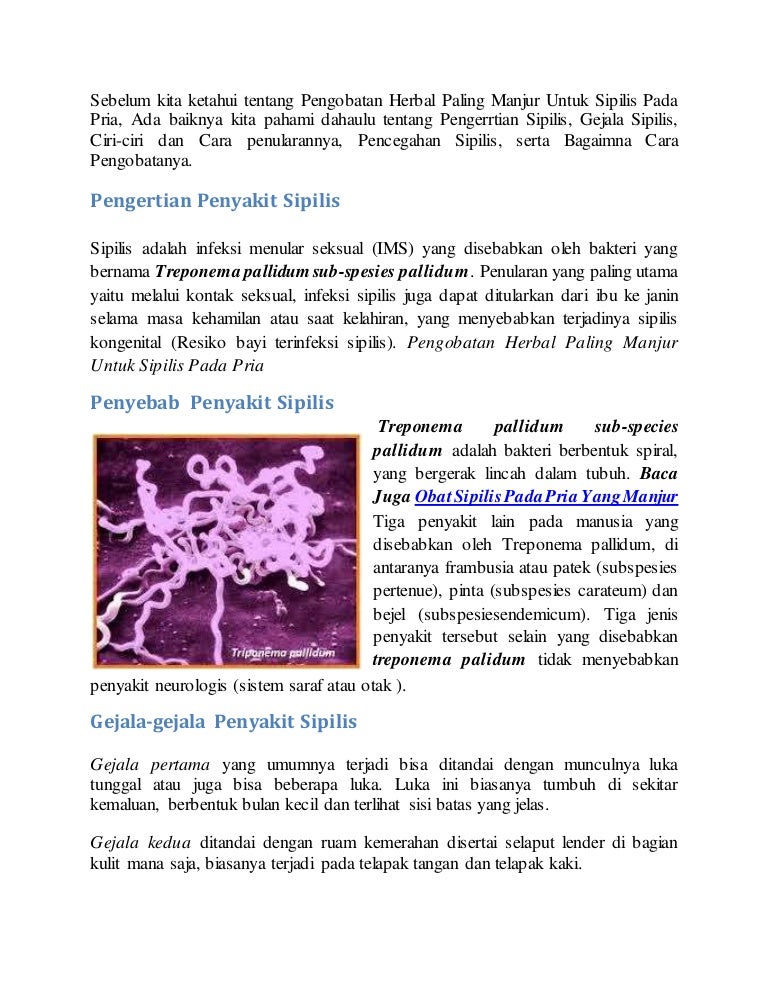

PENYAKIT SIPILIS PADA PRIA. Penyakit Sipilis Pada Pria | by Apotik Denature | Medium

PENYAKIT SIPILIS PADA PRIA. Penyakit Sipilis Pada Pria | by Apotik Denature | Medium

Pengobatan gejala sipilis pada pria yang manjur dan aman

Pengobatan gejala sipilis pada pria yang manjur dan aman